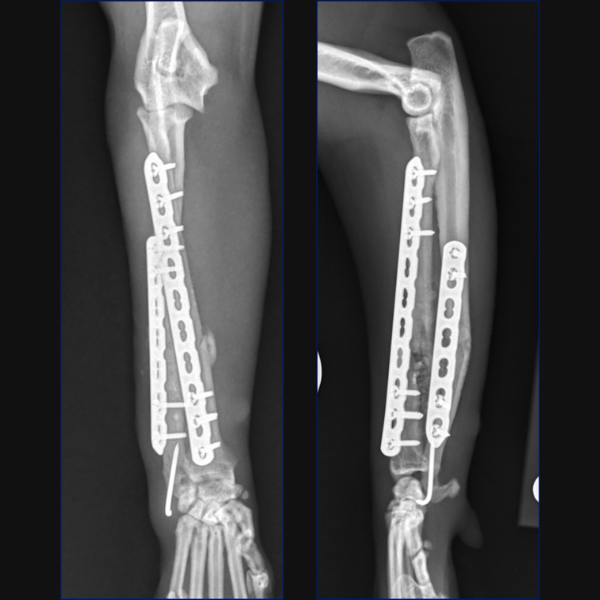

Separate minimally invasive approaches were made for the radial and ulnar fractures to facilitate placement of a 10-hole 1.5/2.0 LCP cranially on the radius with 3 screws proximally and 3 distally. A 7-hole 1.5/2.0 LCP was then placed laterally on the ulna through proximal and distal stab incisions. Lastly, the ulnar styloid fracture was stabilized minimally invasively through a stab incision using a 1.2mm K-wire.